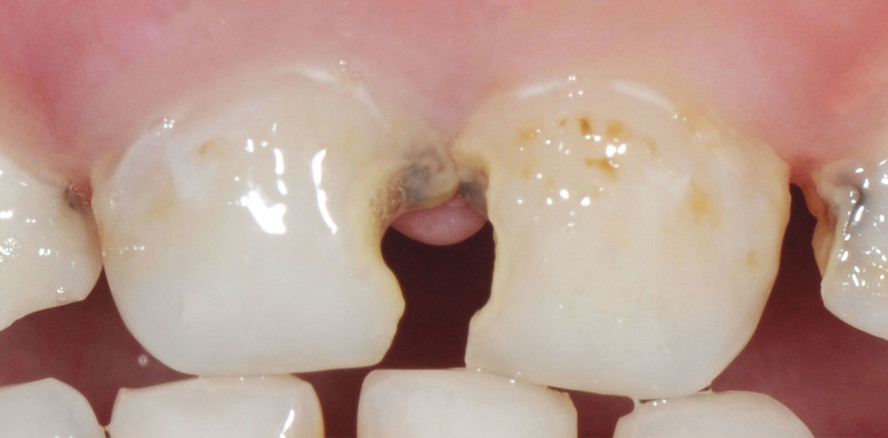

Ein 4-jähriges Mädchen wurde mit Beschwerden über schmerzende Zähne beim Essen und unansehnliche Frontzähne in die pädiatrische Klinik von Dr. Kunal Gupta in Neu-Delhi, Indien, überwiesen. Die klinische Untersuchung zeigte große kariöse Läsionen an den obe­ren Frontzähnen (Abb. 1). Die Röntgenuntersuchung zeigte eine Freilegung der Pulpa an den Zähnen 51 und 61 mit weit geöffneten Wurzelspitzen. Die Ziele des Behandlungsplans waren zunächst die Linderung der Schmerzen und die Beseitigung der Pathologie und dann die Wiederherstellung von Funktion und Ästhetik. Nach dem Einsetzen des Kofferdams wurde an 51 und 61 eine routinemäßige endodontische Behandlung durchgeführt und die Kanäle mit Guttapercha gefüllt und mit AH Plus™ (Dentsply Sirona) versiegelt. Da die Ästhetik im Vordergrund stand, wurden die vier Frontzähne mit Ceramir Pediatric Crowns versorgt. Zur Bestimmung der geeigneten Größe wurde eine (vom Hersteller mitgelieferte) Messlehre verwendet, mit der die Kronen in der richtigen Größe ausgewählt wurden (Abb. 2). Die gesamte Karies wurde mit einem runden Diamantschleifer entfernt, und die mesiale und distale Reduktion erfolgte mit einem feinen konischen Dia­mantschleifer, um die interproximalen Kontakte zu öffnen und die zirkumferenzielle Reduktion einzuleiten. Die bukkale und linguale Reduktion erfolgte mit einem konischen Runddiamanten. Alle Ränder und das Ausmaß der Reduktion wurden von der Karies diktiert und auf ein Minimum beschränkt, um so viel Zahnsubstanz wie möglich zu erhalten, wobei die Ränder supragingival gehalten wurden (Abb. 3).